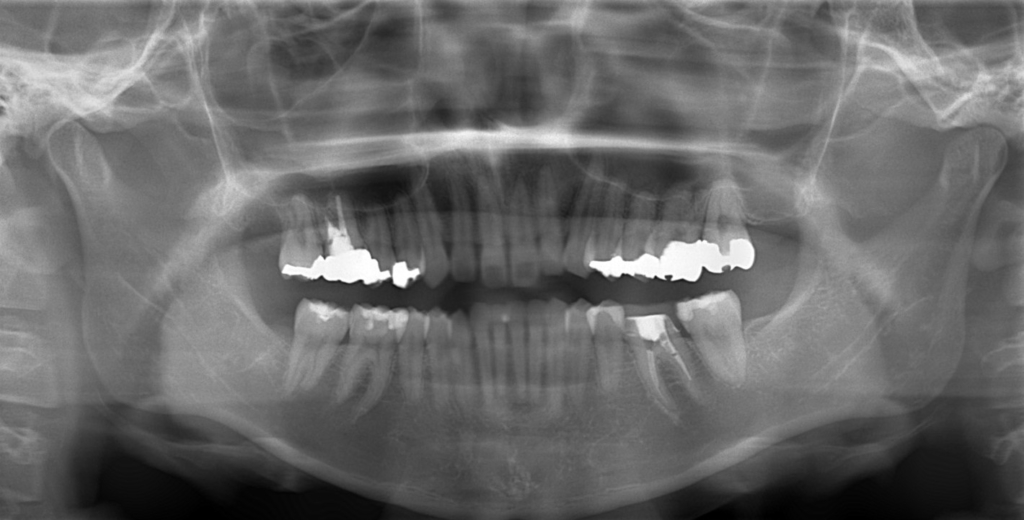

レントゲン写真で確認すると、

この患者さんの場合、

#1.上顎前歯部が下方へ位置していることによるガミースマイル

#2.上下顎前突(歯槽性)

噛み合わせの関係はノーマル。

と診断しました。